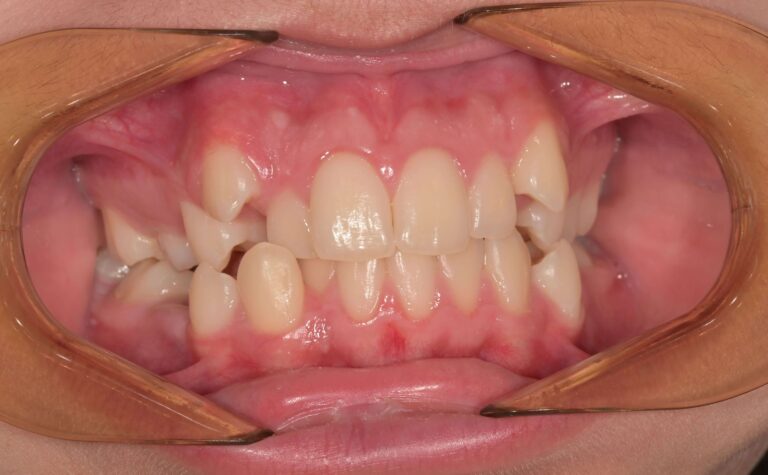

Кръстосана захапка (Crossbite)

Кръстосаната захапка е ортодонтски проблем, при който горните зъби застават зад долните. Дължи се на несъответствие в челюстите, което поражда неправилно подреждане на зъбите (включително млечните зъби). Може да засегне един, няколко зъба или цялото съзъбие. Има два основни вида кръстосана захапка:

Задна кръстосана захапка – По-често срещана от двата вида. Възниква, когато горните задни зъби попадат зад долните задни зъби.

Предна кръстосана захапка – среща се по-рядко. При затворена уста горните предни зъби са разположени зад долните предни зъби.

Усложнения, които могат да настъпят – ако не се лекуват, кръстосаните захапки могат да доведат до изместване на челюстта на едната страна, което от своя страна води до неравномерен растеж на челюстта и износване на зъбния емайл. Кръстосаната захапка често води до заболявания на венците.